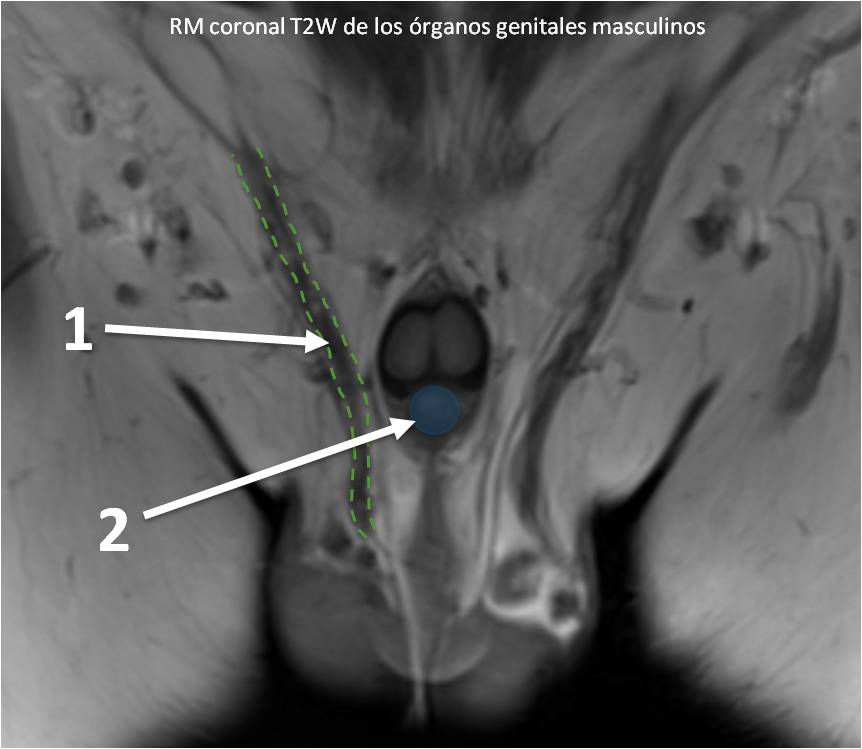

} Identifique las estructuras señaladas:

" Identifique las estructuras señaladas

; Identifique las estructuras señaladas:

& Identifique las estructuras señaladas